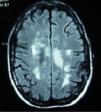

Clinical casesCase 1: 34-year-old Caucasian female, with a history of optic neuritis of the right eye 8 years ago. After admission due to abdominal discomfort, vomiting and fever, she presented 48h of ascending numbness and weakness of the lower limbs, urine and stool retention and decreased visual acuity of the left eye. During the interrogation in search of connective tissue diseases she referred xerostomia, xerophthalmia, vaginal and skin dryness. Neurological examination showed paraparesis with muscle balance of 1/5 in the left lower limb, 0/5 in the right lower limb and 2/5 in the right upper limb, diffuse hyperreflexia, extensor cutaneoplantar reflex, hypoesthesia for thermal sensitivity and in the painful D4-D5 dermatome, predominantly right deep sensitivity deficit in the left leg. Bilateral lower Schirmer test 5mm. Blood tests showed ESR 48mm/h, C-reactive protein 2.74mg/dl, antinuclear antibodies (ANA) speckled pattern +1/320, positive anti-Ro/SSA and aquaporin 4 antibodies and negative antiphospholipid antibodies. Vitamin B 12, folic acid, serology (syphilis, Brucella, Borrelia, HIV, HCV, HBV), Bence Jones protein, cryoglobulin, copper, serum levels of angiotensin converting enzyme, homocysteine and coagulation were normal. Magnetic resonance imaging (MRI) of cervical and thoracic spine: intramedullar lesion from C5 to D2. Cranial MRI (Fig. 1): presence of multiple lesions in the white matter on T2 and FLAIR. Evoked potentials: P100 response bilaterally elongated, being higher on the right side. Diagnosed with SS, treatment with boluses of methylprednisolone was initiated intravenously followed by oral prednisone at 50mg/day and azathioprine, achieving a progressive increase in visual acuity, although still with a temporal peripheral superior scotoma in the right eye. There was recovery of muscle balance and control of sphincters, walking without support at 15 months and without a new episode in the past 2 years.

Cranial MRI in T2 and FLAIR sequences, with presence of multiple lesions in the white matter at the subcortical, periventricular, periauricular and right corona radiata levels. The largest lesion extends from the posterior limb of the right internal capsule to the right mesencephalic peduncle.